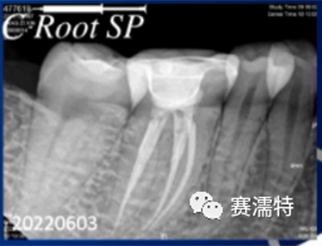

C-Root SP是預(yù)混合的、可即刻應(yīng)用的、可注射的、遇水凝固的硅酸鹽類生物活性陶瓷糊劑材料,主要成分為硅酸鍶、氧化鋯、磷酸鈣、氫氧化鈣,用于根管的密封和永久充填,適合單尖法、側(cè)壓法和熱牙膠法。 C-Root SP為世界口腔醫(yī)生提供一個“鍶生物陶瓷”的新選擇! >>>

張云鳳老師案例